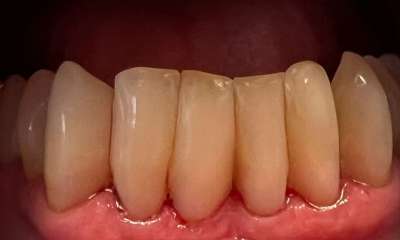

Bioclear composite treatment to get rid of "black triangles" and spaces between lower front teeth. These spaces are common on teeth that have had gum recession and roots exposed.